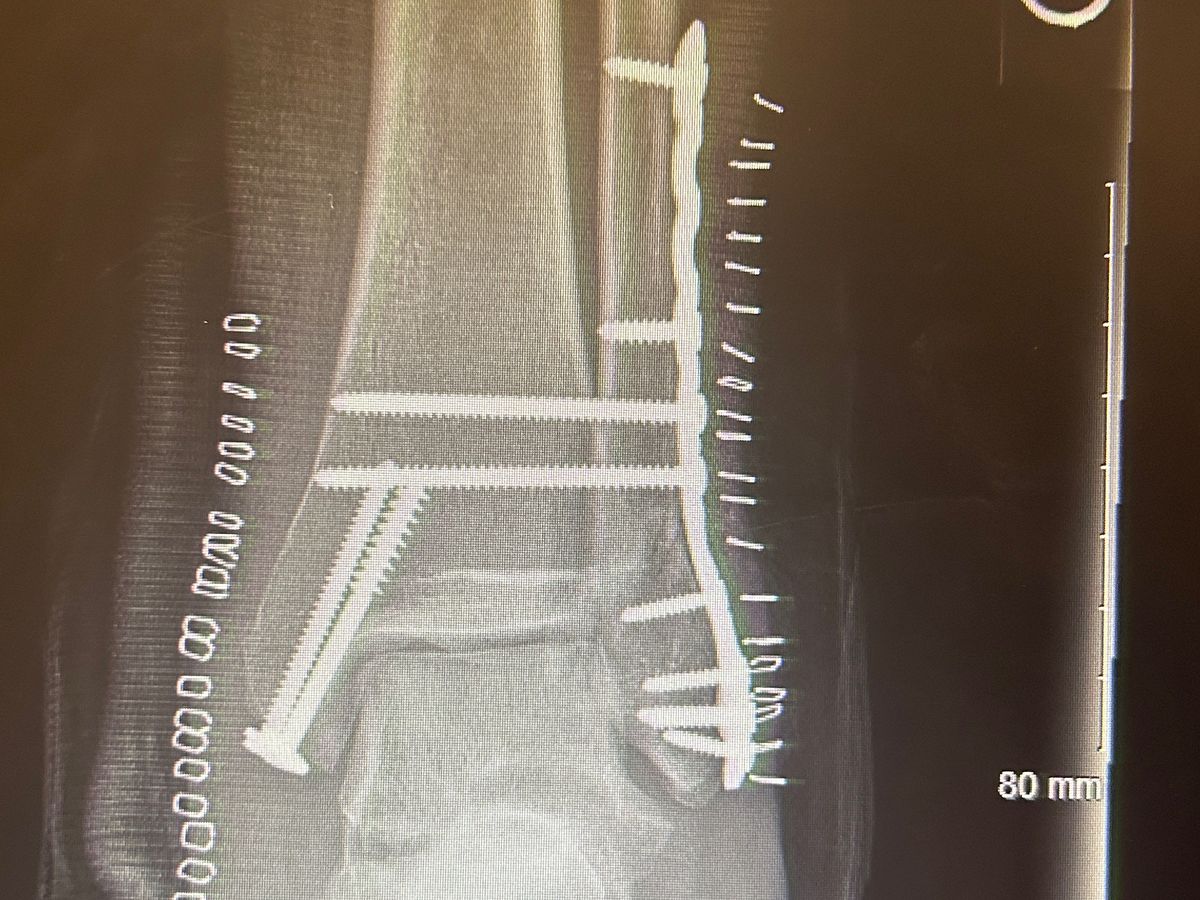

Hey guys, I just got into a bad motor-vehicle accident on March 5th, where I broke my left wrist and I had to get surgery in my left ankle. I’m currently immobile for the next few months and honestly, It’s overwhelming. I need help to pay off the expenses for surgery and for other basic needs like food and therapy during my recovery. anything helps.